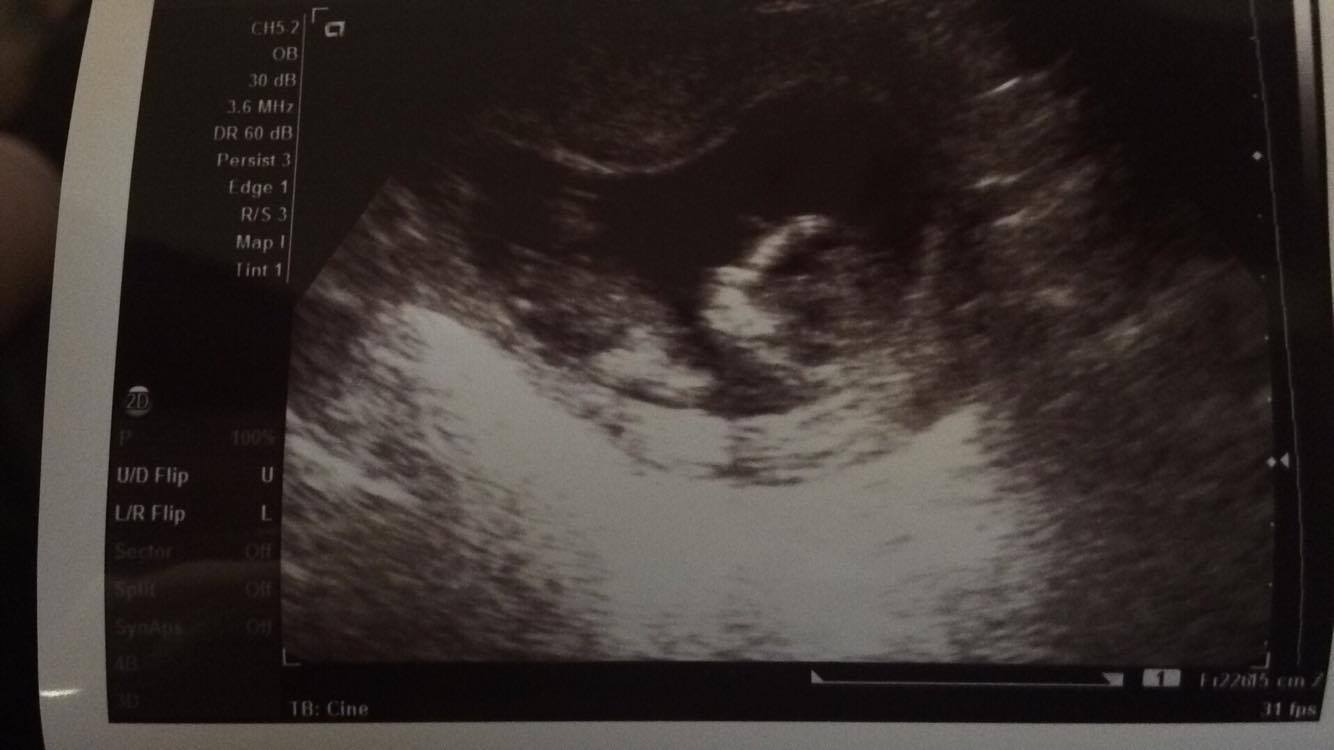

My friend asked me to post these for guesses for her baby. Please let us know if you think boy or girl or if you can't tell from these pictures. Thank you!

Possibly girl but not the best pictures x

Not sure there is a nub, but I'll give a very slight girly guess.